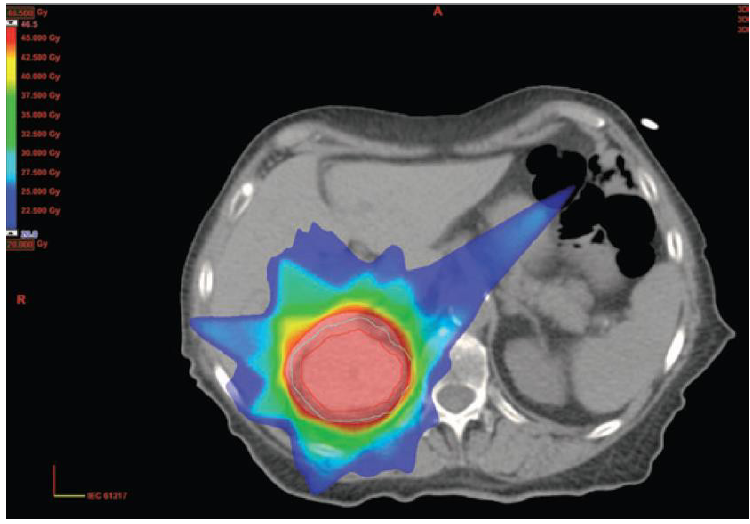

3) STEREOTAKTICKÁ ABLACE PRIMÁRNÍHO NÁDORU LEDVINY

- Aplikace vysoké dávky radioterapie na frakci (až 20Gy) ve více frakcích

- překonání radiorezistence RCC

- aktivace apoptózy endotelií ceramidovou dráhou, výhodné u vaskularizovaných nádorů

- Nádory do 5 cm bez lymfadenopatie a vzdálených metastáz (T1N0M0)

- Tam kde nelze operovat: solitární ledvina, bilaterální karcinom, stav pacienta, lokální recidiva po předchozí resekci..

- Review 7 retrospektivních a 3 prospektivních studií (Siva 2012)

- Celkem 126 pacientů, 1-6 frakcí SABR – nejčastější režim 5x8 Gy

- Medián sledování 9-57.5 měsíců

- Souhrnná lokální kontrola 94% (84-100%)

- Souhrnná toxicita grade 3 pouze 3.8% (0-19%)

- Souhrnná toxicita grade 1/2 pouze 21% (0-93%)